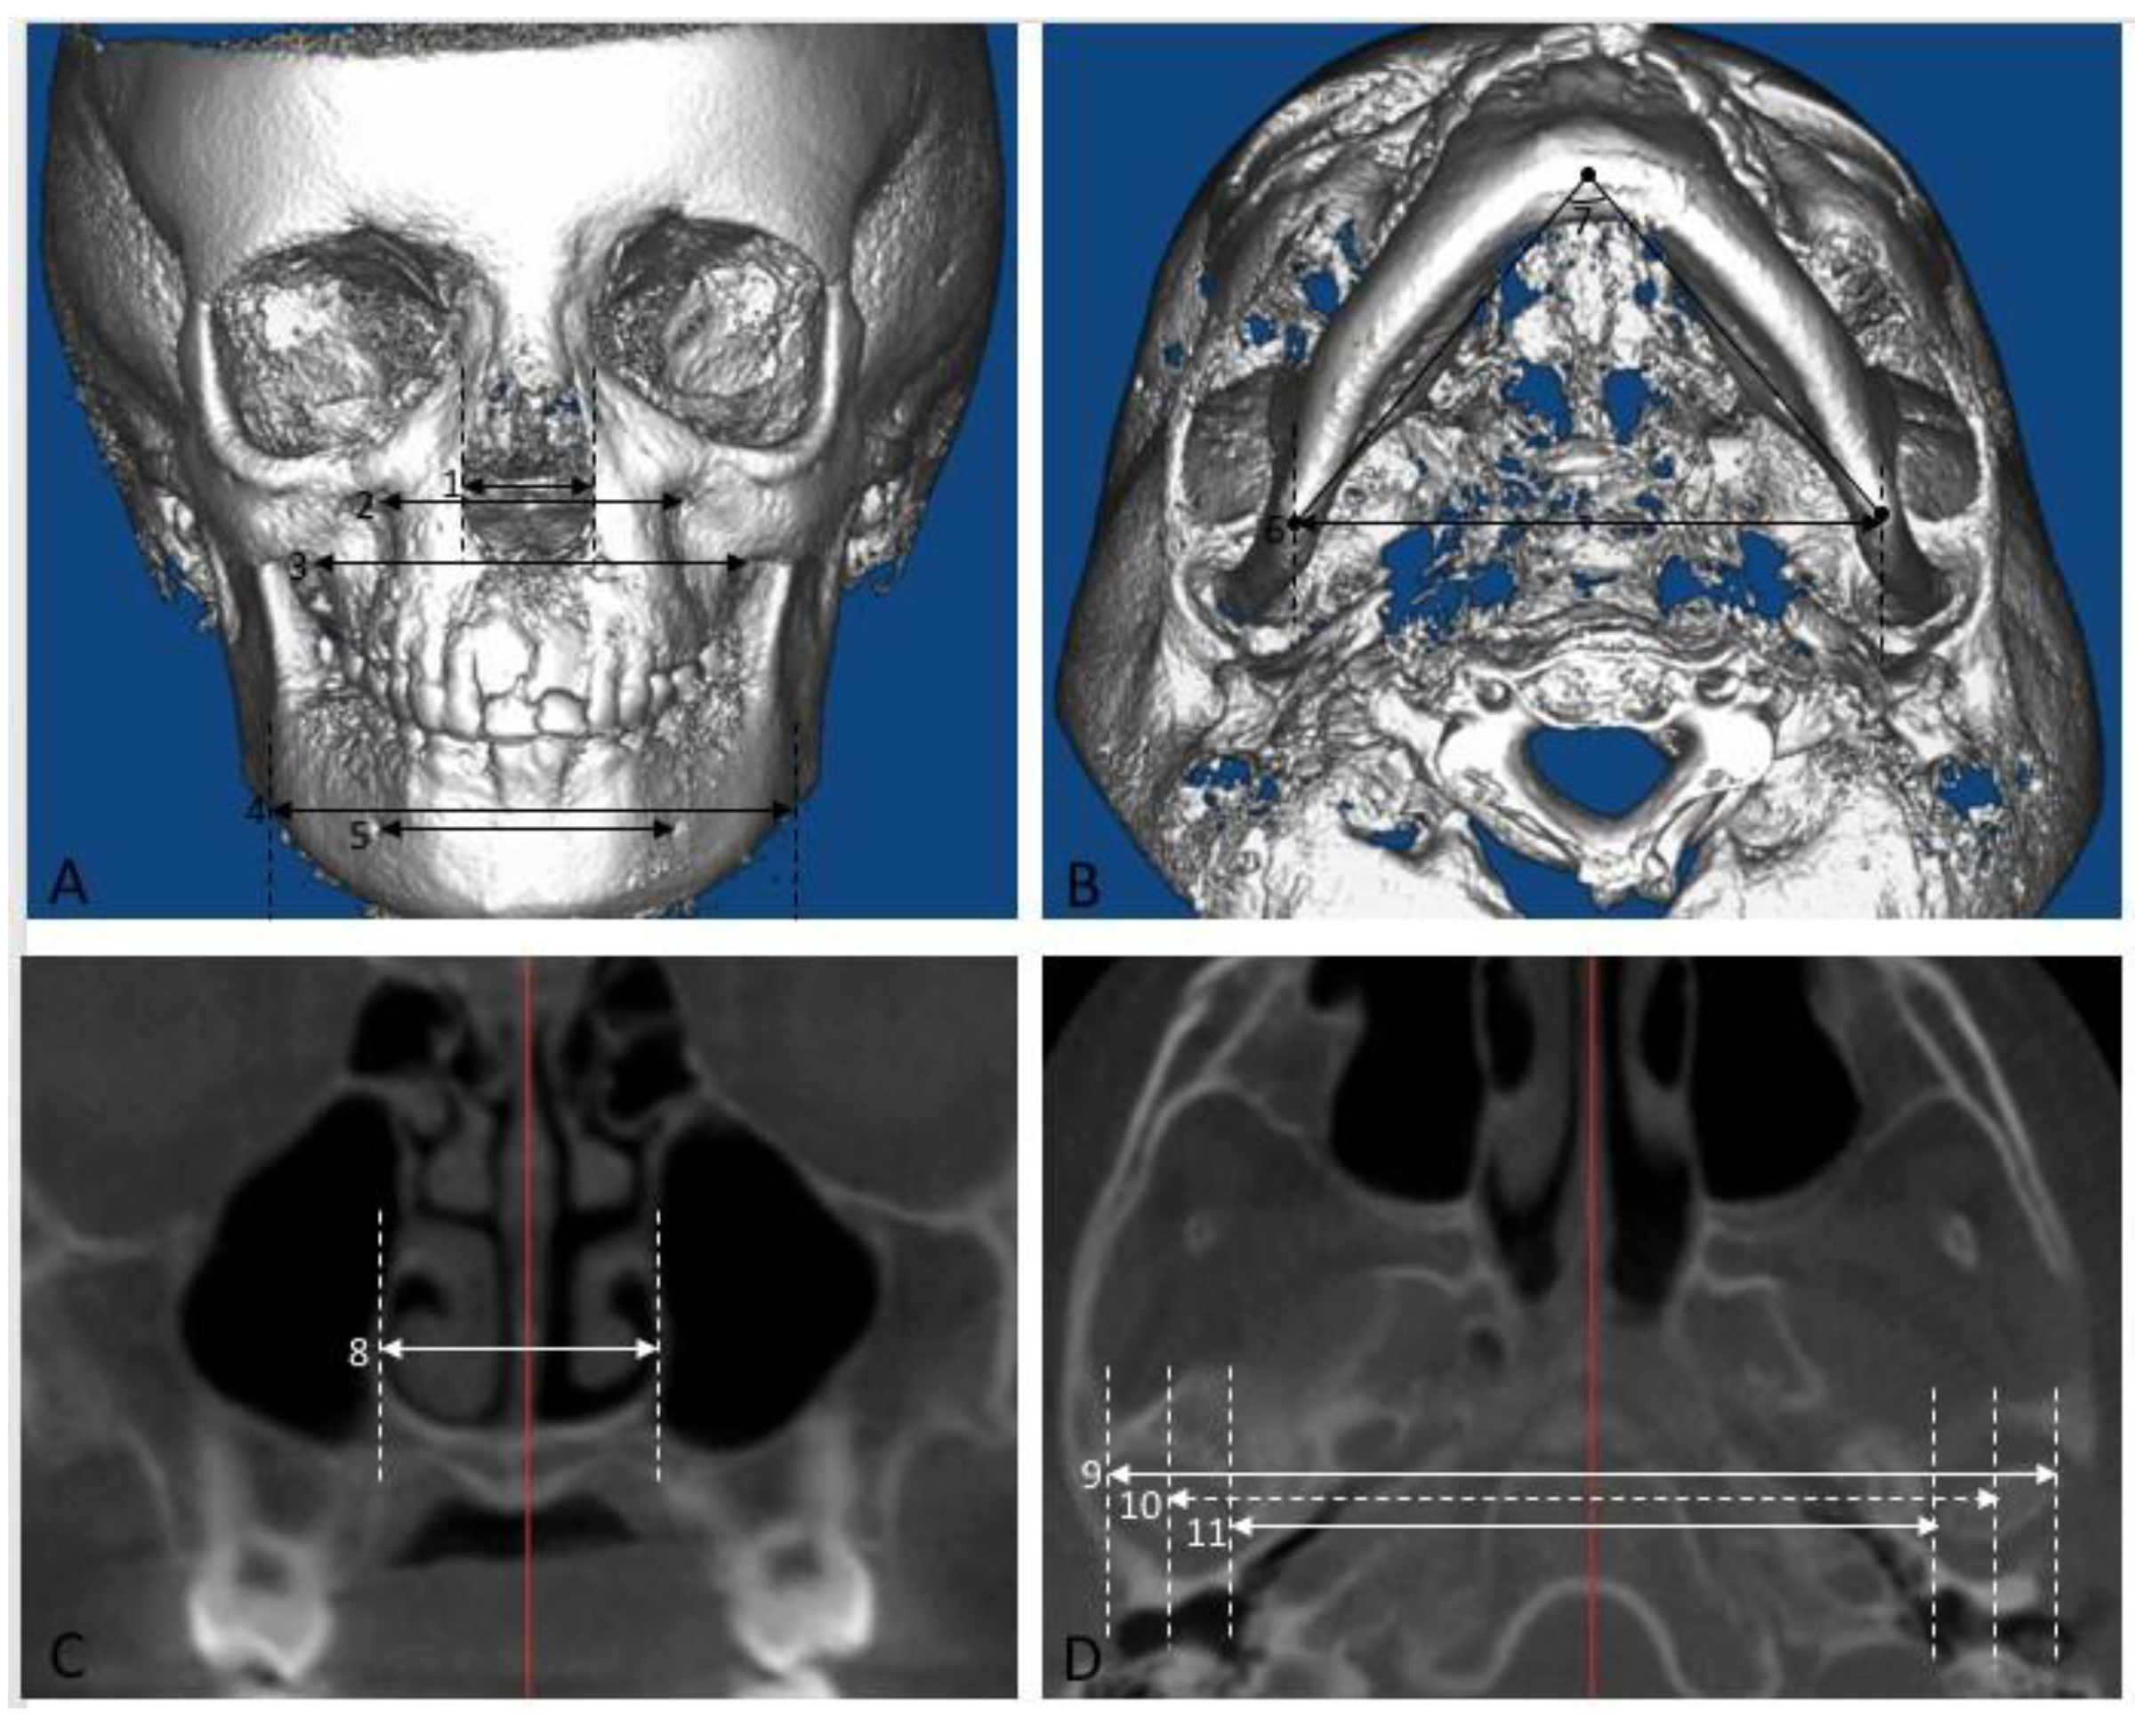

- Roll: The cranium was oriented such that a midline could be drawn through the midpoint of the frontonasal suture and base of the nose and is parallel to the true vertical (Figure 1A). In addition, a true horizontal line goes through the most inferior aspect of the orbits.

- Yaw: The cranium was oriented to achieve the best symmetry of the cranium, zygomatic, and maxillary structures on either side of the midline (Figure 1A).

- Pitch: For measurements on the non-tooth-bearing, skeletal features of the face, the cranium was oriented such that the Frankfort horizontal plane was parallel to the true horizontal plane (Figure 1B). For measurements on the tooth-bearing, dentoalveolar areas, the cranium was oriented such that the functional occlusal plane was parallel to the true horizontal plane (Figure 1C).

- Anterior nasal width: when viewed from the frontal, the distance between the most convex point along the lateral nasal margins.

- Io-Io: when viewed from the frontal, the distance between the mesiodistal and inferosuperior center of the infraorbital foramen.

- Mx-Mx: when viewed from the frontal, the distance between the most concave point in the infrazygomatic area.

- Ag-Ag: when viewed from the frontal, the distance between the most concave point in the lower mandibular border.

- Mf-Mf: when viewed from the frontal, the distance between the most mesial margin of the mental foramen.

- Go-Go: when viewed from the inferior, the distance between the mesiodistal center at the most infero-posterior point of the inferior mandibular border.

- Gonion triangle: when viewed from the inferior, the angle between the left and right gonion and menton. The points are identified on a profile view and the angle lies in the axial plane.

- U6 nasal width: the distance between the most convex point along the lateral nasal wall on a coronal section at the mesiodistal center of the maxillary 1st molar.

- Cd-Cd lateral: the distance between the most lateral points of the condyle that could be seen on axial cross sections of the condyle.

- Cd-Cd middle: the average of Cd-Cd medial and Cd-Cd lateral and represents the midpoint of the condylar head.

- Cd-Cd medial: the distance between the most medial points of the condyle that could be seen on axial cross sections of the condyle.